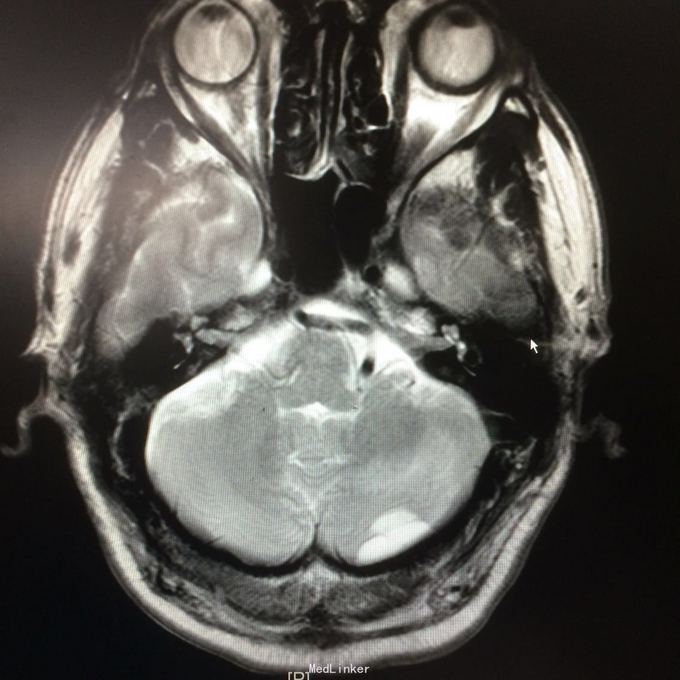

主诉:头晕头痛2年 病史:2年前无明显诱因出现头痛,呈刺痛,程度较重,伴头晕、天旋地转感,1年前查头颅MR提示:左侧小脑半数囊性病变,考虑血管母细胞瘤

查体:神志清楚,病理证阴性 辅助检查:头颅MR提示左侧小脑半数后部囊状占位灶,考虑良性病变。

诊断:左侧小脑血管母细胞瘤 处理:行左侧小脑占位病变切除术,术后病理提示:符合血管母细胞瘤。